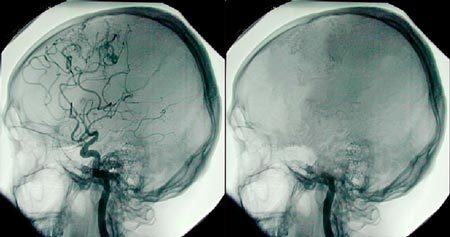

Một người được coi là chết não khi anh/cô ta không còn hoạt động thần kinh ở bộ não hoặc cuống não, tức là không có xung điện nào được phát đi giữa các tế bào não. |

Một người được coi là chết não khi anh/cô ta không còn hoạt động thần kinh ở bộ não hoặc cuống não, tức là không có xung điện nào được phát đi giữa các tế bào não. Theo tiến sĩ Diana Greene-Chandos, giáo sư chuyên ngành thần kinh học và phẫu thuật thần kinh thuộc Trung tâm y tế Wexner, Đại học Ohio (Mỹ), các bác sĩ sẽ tiến hành hàng loạt cuộc kiểm tra để xác định liệu ai đó có bị chết não hay không.

Một trong số các cuộc kiểm tra đó nhằm xem liệu đối tượng có thể tự xúc tiến việc thở của mình - một phản xạ rất căn bản do gốc não điều khiển. "Đó là thứ cuối cùng bị mất đi", bà Greene-Chandos cho biết.

Ở Mỹ và nhiều nước khác, một người được pháp luật công nhận là đã chết nếu anh/cô ta vĩnh viễn mất mọi hoạt động não (chết não) hoặc tất cả các chức năng hô hấp và tuần hoàn máu. Trong trường hợp của Jahi, 3 bác sĩ đã kết luận rằng cô bé bị chết não.